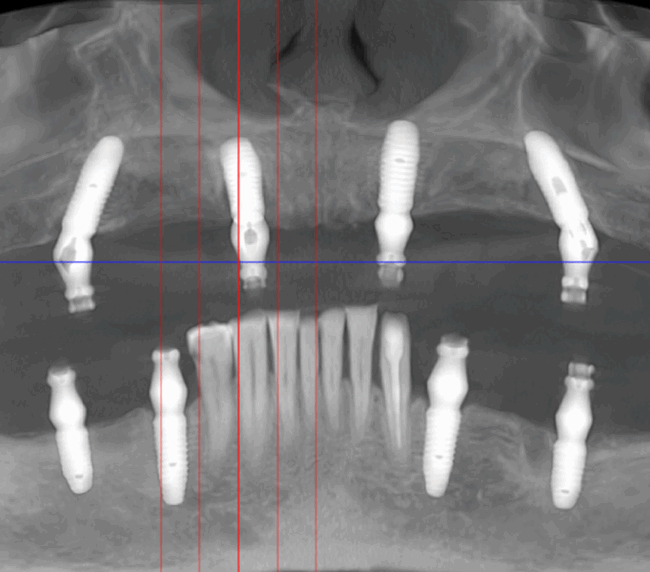

anul 1998, dr. Paulo Malo a introdus pentru prima dată conceptul All-on-4 în reabilitarea orală a pacienților, obținând rezultate remarcabile. De atunci, mii de pacienți au beneficiat cu succes de această tehnică. Sistemul de implanturi utilizat inițial în acest concept a fost Nobel Biocare, o companie cu o vastă experiență și o bază solidă de pacienți tratați, susținută prin numeroase

studii științifice.În cazurile de atrofie osoasă severă, când inserarea implanturilor în zonele laterale nu este posibilă fără adăugare osoasă, conceptul All-on-4 prevede plasarea implanturilor în unghiuri strategice pentru a evita zonele deficitare. Astfel, două implanturi sunt plasate în zona incisivilor laterali, iar alte două în zona premolarilor.

- 4 implanturi;

- 2 multiunit-uri drepte și 2 multiunit-uri angulate, conform necesităților protetice;